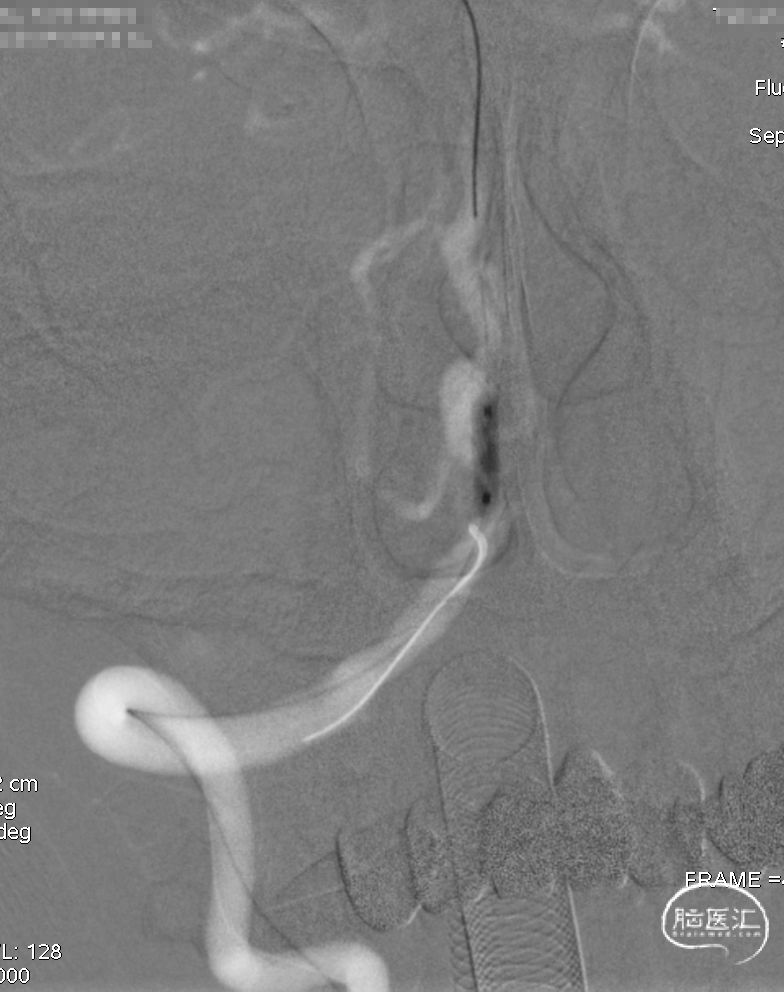

DSA示双侧椎动脉V4段狭窄,右侧为著且合并梭形动脉瘤。

术前DSA。